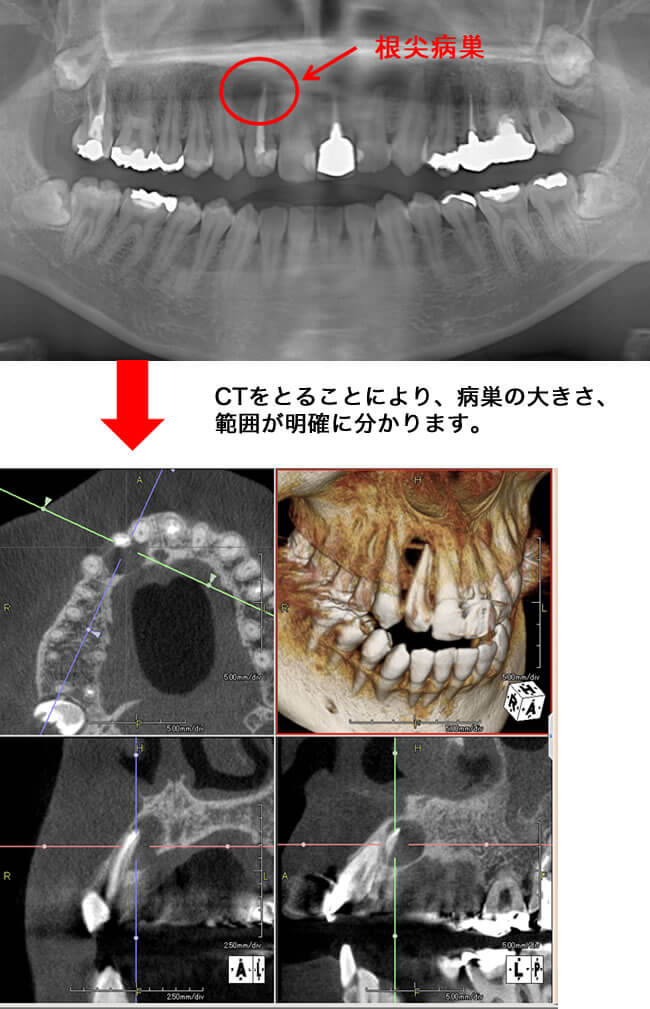

根管治療

・歯根の先端の病巣発見や、治療後の治癒の状態など、今までの二次元のレントゲン診断に比べかなり正確に把握できます。

歯科用CT画像を使った正確な診断によって、根の病気の完治を目指しやすくなります。